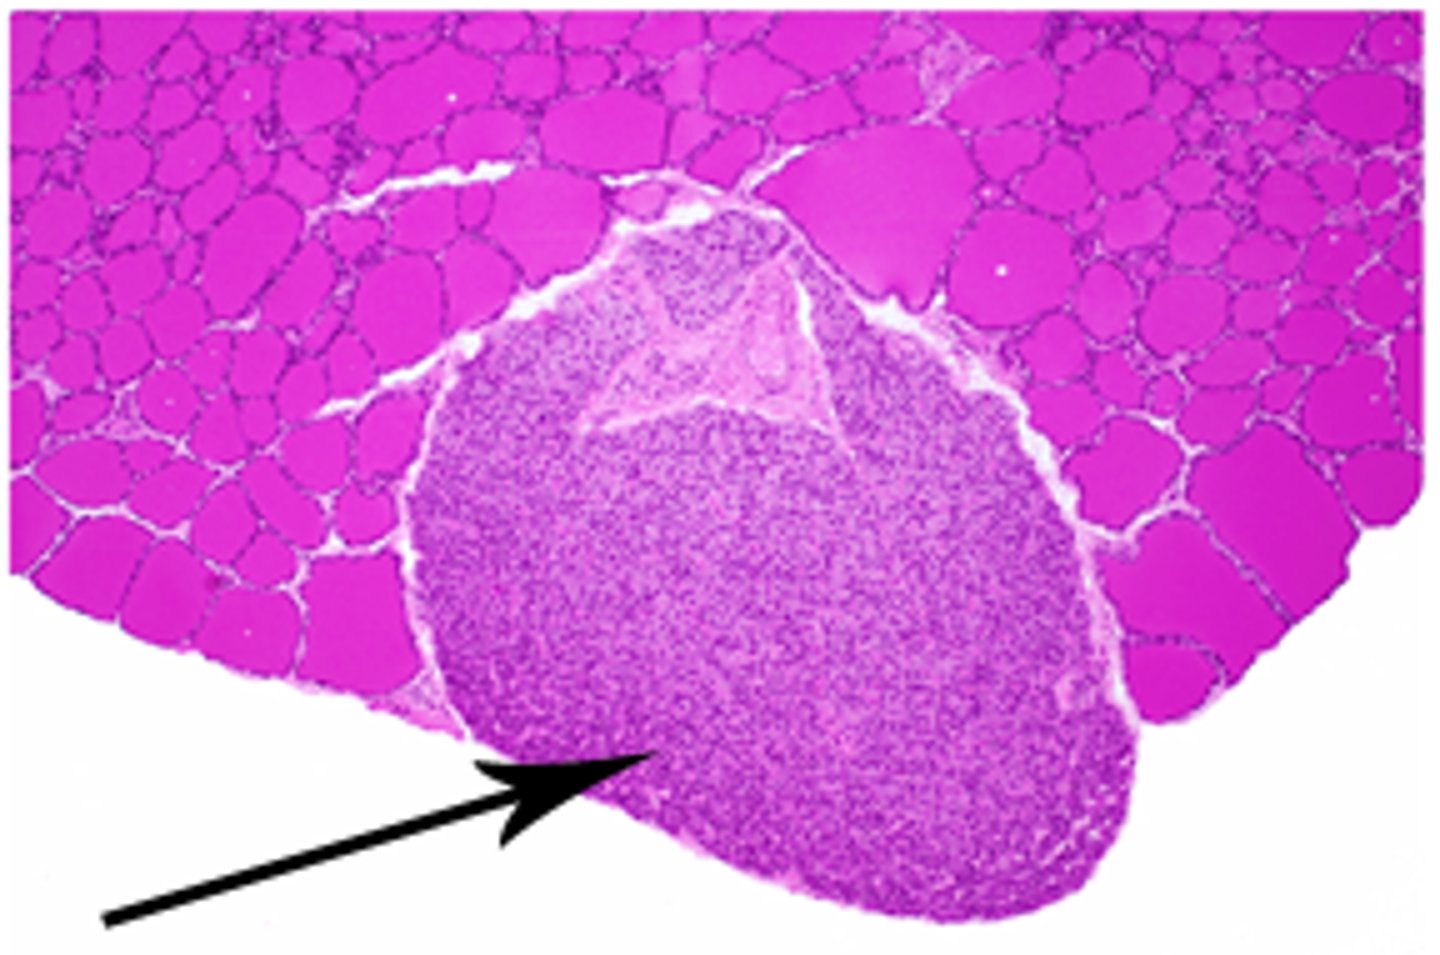

pancreas

what organ is this slide from

pancreatic islets of langerhans of pancreas

2

pancreatic acini (exocrine cells) of pancreas

1